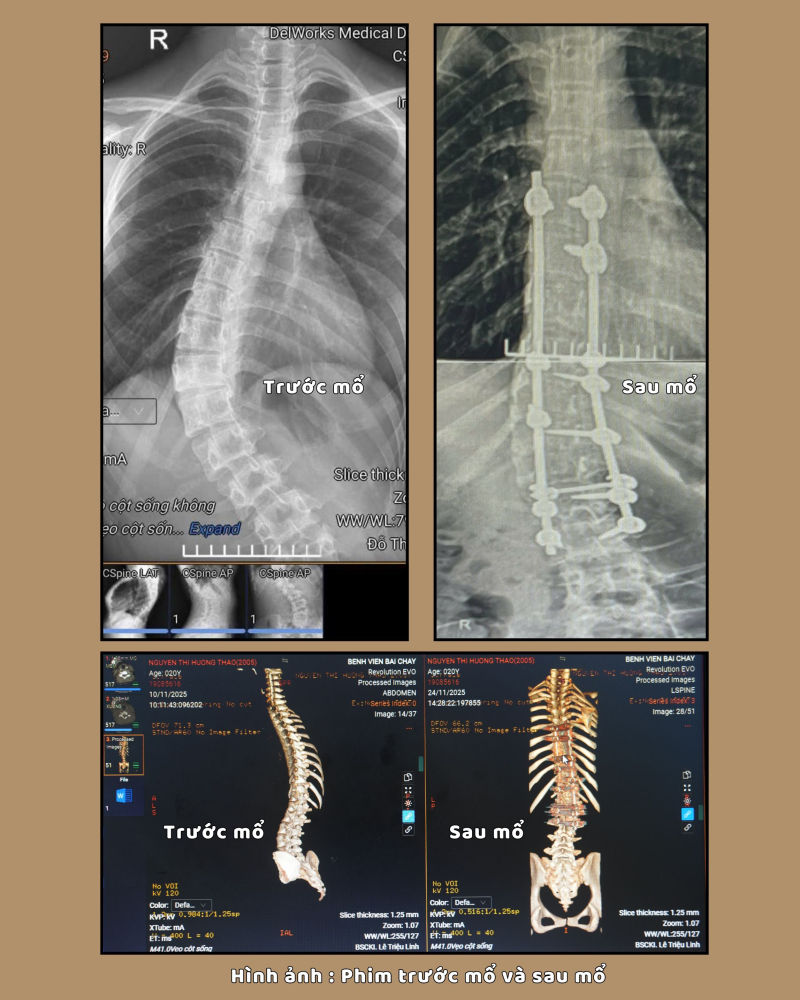

Khi vào viện được các bác

sĩ thăm khám và cho làm các xét nghiệm cần thiết. Kết quả chụp cắt lớp vi tính

cho thấy: Hình ảnh vẹo cột sống/nẹp cố định đốt sống từ D6 đến L3. Gãy cung sau

một số thân đốt sống và được chẩn đoán: Vẹo cột sống mức độ nặng, có chỉ định

phẫu thuật chỉnh vẹo cột sống.

Kíp phẫu thuật do bác sĩ CKII Lê Triệu Linh, Phó trưởng khoa Ngoại thần kinh – Lồng ngực, Bệnh viện Bãi Cháy cùng ê kíp phẫu thuật đã tiến hành phẫu thuật giải phóng cấu trúc biến dạng, chỉnh trục cột sống và cố định bằng các thanh nẹp – vít chuyên dụng. Sau mổ, cột sống được đưa về trục cân đối tự nhiên, giải phóng áp lực lên các rễ thần kinh.